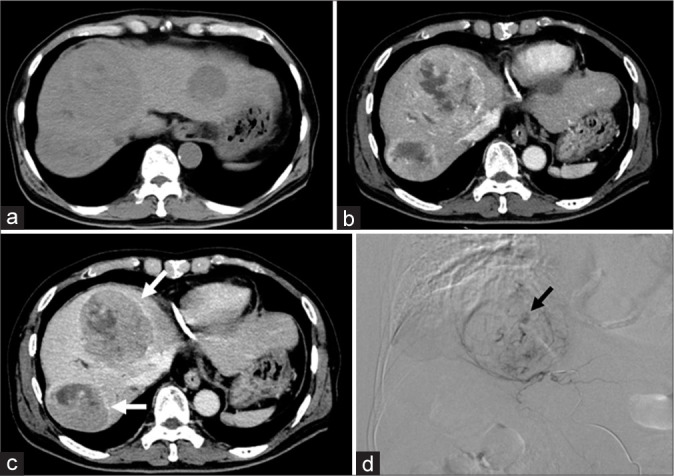

Material and methods: Forty-nine initial DEB-TACE procedures in 49 patients between November 2010 and April 2024 were included in this retrospective study. VLP was defined as a localized pooling of contrast agents within the tumor in the venous phase of digital subtraction angiography. The laboratory data, pre-treatment imaging findings such as the maximum tumor diameter (≥3 cm or <3 cm) and the presence of enhancing capsule obtained from computed tomography or magnetic resonance imaging, size of DEBs, and loading drugs, the total number of previous interventional treatments were recorded and compared between VLP occurrence and VLP non-occurrence groups. The multivariate logistic regression analysis was performed to explore the association of factors in predicting VLP occurrence.

Results: VLP was observed in 16 patients (32.65%) out of 49 patients. The maximum tumor diameter (≥3 cm) and the presence of the enhancing capsule were significantly higher, and the total number of previous interventional treatments was significantly smaller in the VLP occurrence group than in the VLP non-occurrence group (P = 0.0006, 0.0007, and 0.0003). In multivariate analysis, the maximum tumor diameter, the presence of the enhancing capsule, and the total number of previous interventional treatments were significantly associated with the occurrence of VLP (P = 0.0048, 0.0093, and 0.047).